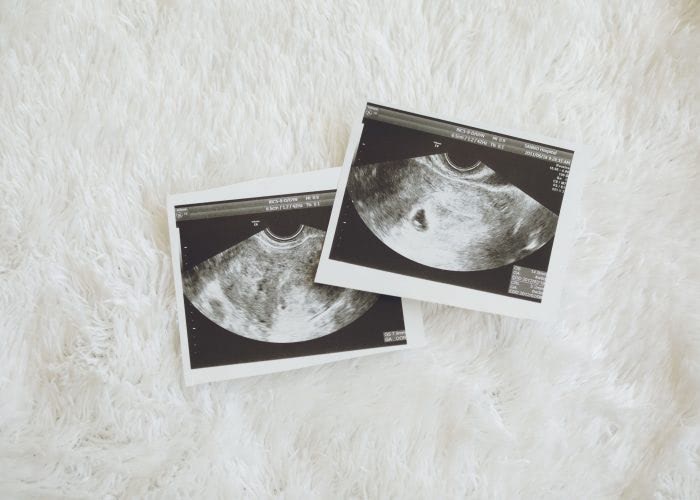

妊娠7週で心拍が確認できてホッとしていたところ、トイレで茶褐色のごく少量の出血に気づきました。

5. 内診&超音波検査

外陰部の視診や触診、腟鏡を使って腟内の状態確認を内診台の上で行います。外側からは見ることができない子宮や卵巣の内部は超音波で検査します。不妊治療における超音波検査は、内科の聴診と同様の位置づけだと考えましょう。